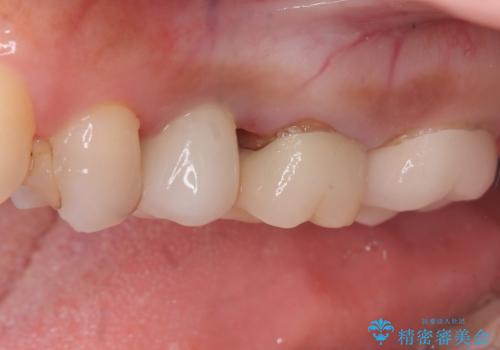

左上第一小臼歯のインプラント治療

- 患者様は、左上第一小臼歯の垂直性歯根破折が確認され、抜歯が必要となりました。本来、抜歯即時埋入を適用できるケースでしたが、患者様のご都合によりブリッジとインプラントで一度悩まれるとのことで待時埋入となりました。治療計画では、上顎の骨の状態を慎重に評価し、デンサーバーを用いてドリリングを行うことで、上顎洞粘膜を傷つけずにインプラントを埋入する方法を選択しました。埋入後の安定を確保するため、術後の経過観察を慎重に行います。